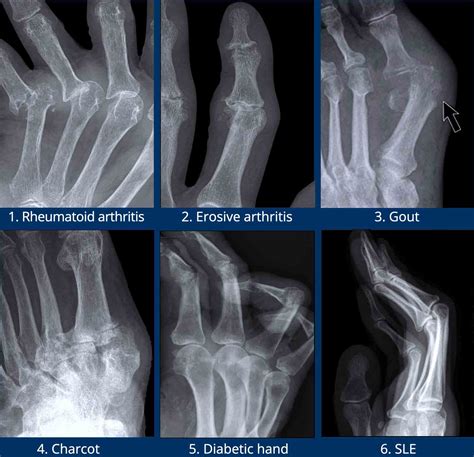

While there are over 100 forms of arthritis, only a few commonly affect the hands. Being able to distinguish between them can help you have a more productive conversation with your healthcare provider.

• Osteoarthritis (OA): Often called "wear-and-tear" arthritis, this is the most common form. It occurs when the cartilage that cushions the ends of your bones gradually deteriorates over time.

• Rheumatoid Arthritis (RA): This is a chronic autoimmune disease where your immune system attacks the lining of your joints (the synovium), causing painful swelling, bone erosion, and joint deformity.

• Gout: While often associated with the big toe, gout can affect the hand joints when uric acid crystals build up in the joint, causing sudden, intense attacks of pain and swelling.

2. Imaging Tests: X-rays are the standard tool to look for cartilage loss, bone spurs, and joint space narrowing. MRI or ultrasound may be used for a more detailed look at soft tissues.